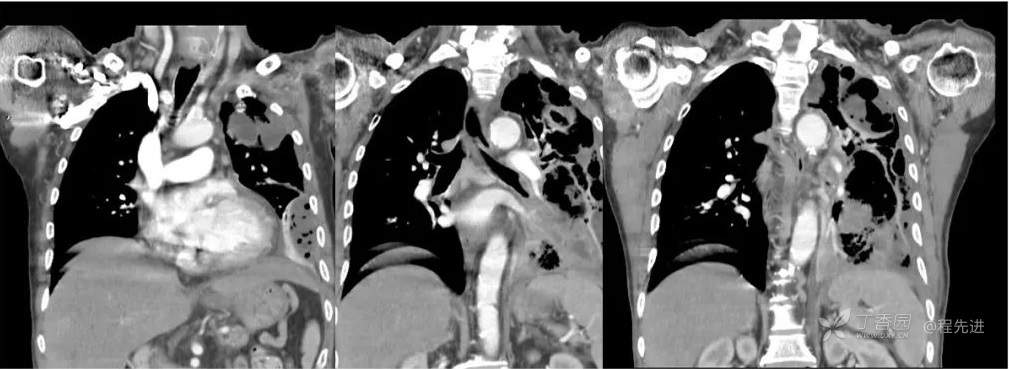

冠状位纵隔窗重建